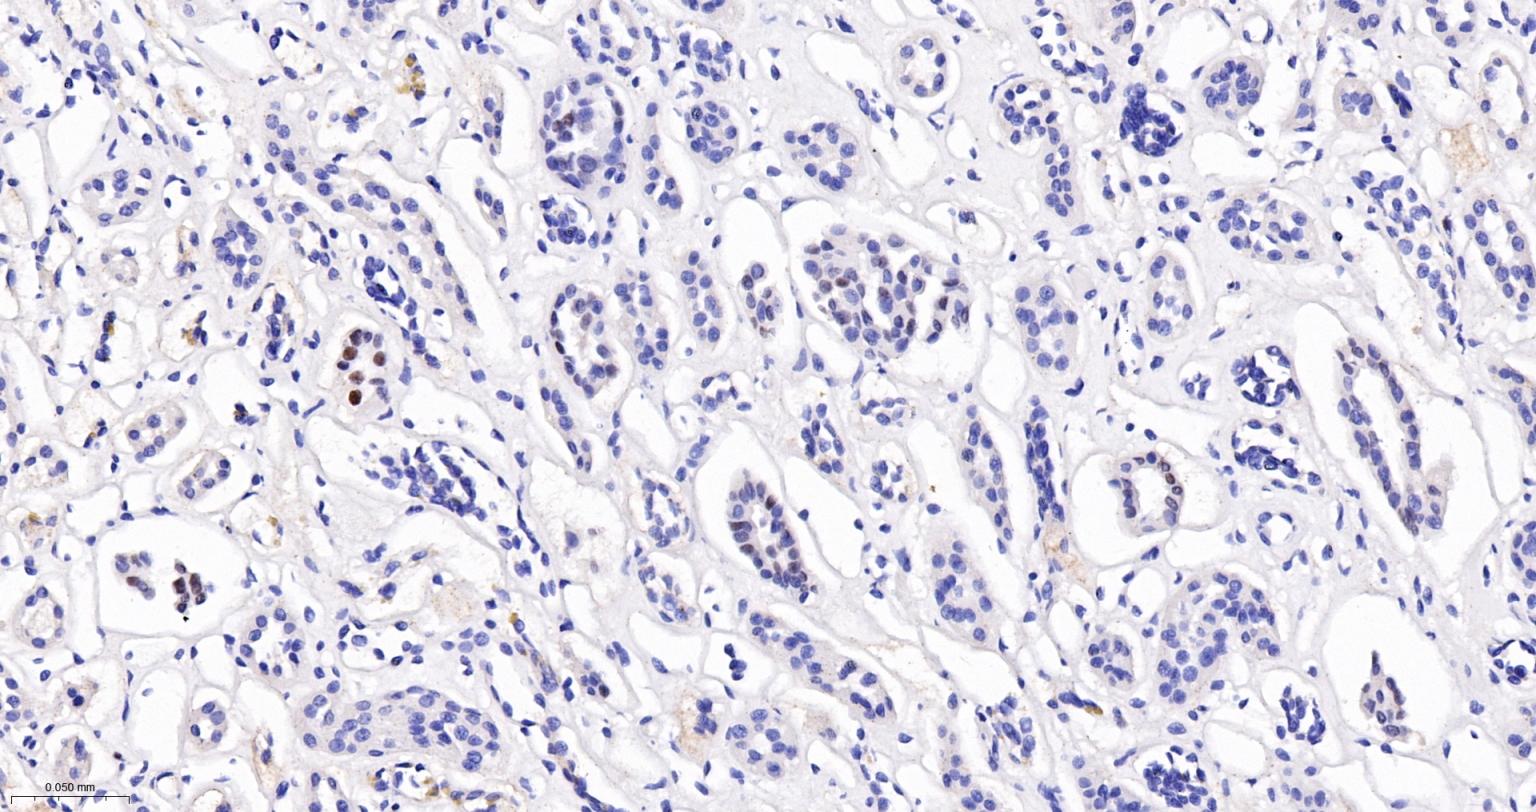

Paraformaldehyde-fixed, paraffin embedded (human breast carcinoma); Antigen retrieval by boiling in sodium citrate buffer (pH6.0) for 15min; Block endogenous peroxidase by 3% hydrogen peroxide for 20 minutes; Blocking buffer (normal goat serum) at 37°C for 30min; Antibody incubation with (phospho-GATA3 (Ser308)) Monoclonal Antibody, Unconjugated (bsm-52157R) at 1:50 overnight at 4°C, followed by operating according to SP Kit(Rabbit) (sp-0023) instructionsand DAB staining.